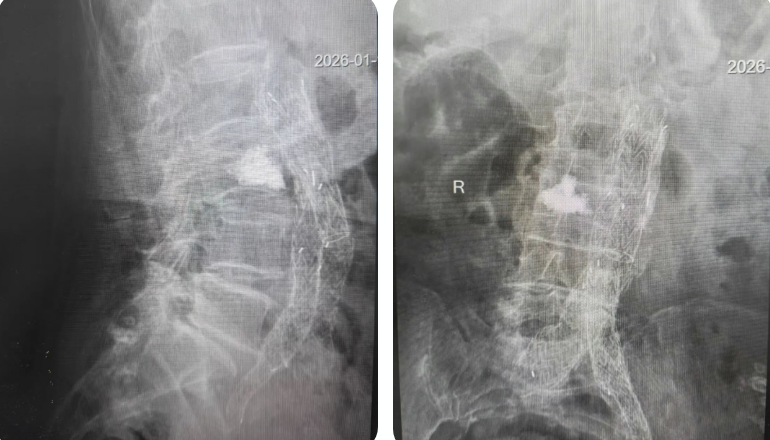

为确保手术安全,科室启动多学科协作机制,联合麻醉科、放射影像科进行术前会诊,共同制定个体化麻醉方案与精准影像引导路径。手术在基础麻醉和局部麻醉下进行,在实时影像引导下,医生经皮穿刺建立微小通道,将球囊精准置入压缩的腰三椎体内,并缓慢扩张球囊复位椎体,随后注入骨水泥强化椎体稳定性。手术创口微小,过程顺利,术中出血少、耗时短,患者未出现任何并发症,真正实现“微创、精准、安全”。